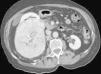

Objetivo. El oncocitoma es un tumor renal benigno, relativamente infrecuente. Hasta este momento su diferenciación radiológica del carcinoma de células renales se considera imposible, aunque hay escasos artículos en que se haya utilizado la tomografía computarizada (TC) trifásica. Los autores describen los hallazgos con TC trifásica en estos tumores, valorando si algunas características, aunque no diagnósticas, sí pudieran sugerir la posibilidad de este diagnóstico. Esto, en algunos casos, podría cambiar el manejo de los pacientes. Material y métodos. Se describen los hallazgos de TC trifásica en 10 casos de oncocitoma, vistos en 8 pacientes (un caso era multifocal-bilateral). En todos los casos el diagnóstico fue anatomopatológico, en la pieza de resección. Resultados. Todos los tumores fueron hallazgos ecográficos incidentales previos a la TC, presentando un tamaño muy variable, de 3 a 15 cm, con una media de 5,2 cm. El contorno era bien definido. Uno de los pacientes tenía tumores bilaterales (2 derechos y 1 izquierdo). Excepto en un tumor, el resto mostraban una cicatriz «estrellada» interna, que en un caso seguía un marcado patrón lobular. La captación tumoral de contraste fue ávida, con una media de 120 HU en fase arterial y 116 HU en fase excretora. La evolución de todos los pacientes fue buena, no detectándose recidivas postquirúrgicas. Conclusiones. Aunque la diferenciación con el carcinoma de células renales no puede hacerse con certeza, debe sugerirse la posibilidad de oncocitoma, fundamentalmente en tumores pequeños, con cicatriz central, ausencia de necrosis, falta de infiltración y un patrón de captación como el que se describe. Independientemente del tamaño, una morfología lobular del tumor también debe sugerir esta posibilidad.

Objective. Oncocytoma is a relatively uncommon benign kidney tumor. To date, it has been impossible to differentiate this tumor from renal cell carcinoma radiologically, although few articles report on the use of tri-phase CT in this tumor. We describe the triphasic CT findings in these tumors and evaluate whether some characteristics, although not sufficient to ensure the diagnosis, can suggest the possibility of oncocytoma. In some cases, this may lead to a different approach to the management of patients. Material and methods. We describe the tri-phase CT findings in 10 cases of oncocytoma in eight patients (one case was bilateral and multifocal). The diagnosis was made after histological examination of surgical specimens in all cases. Results. All the tumors were found incidentally at ultrasound examination prior to CT study. Tumors all had well-defined borders, and their size ranged from 3 to 15 cm, with a mean diameter of 5.2 cm. One patient had bilateral tumors (2 right and 1 left). All but one of the tumors had a star-shaped scar inside, with a marked lobular pattern in one case. All tumors showed avid uptake, with mean enhancement of 120 HU in the arterial phase and 116 HU in the venous phase. All patients evolved favorably with no post-surgical relapse. Conclusions. Although oncocytoma cannot be differentiated from renal cell carcinoma with certainty, the possibility of oncocytoma should be suggested in the case of small tumors with a central scar, without necrosis or infiltration, and an enhancement pattern as described here. Regardless of the size of the tumor, lobular morphology should also suggest this possibility.